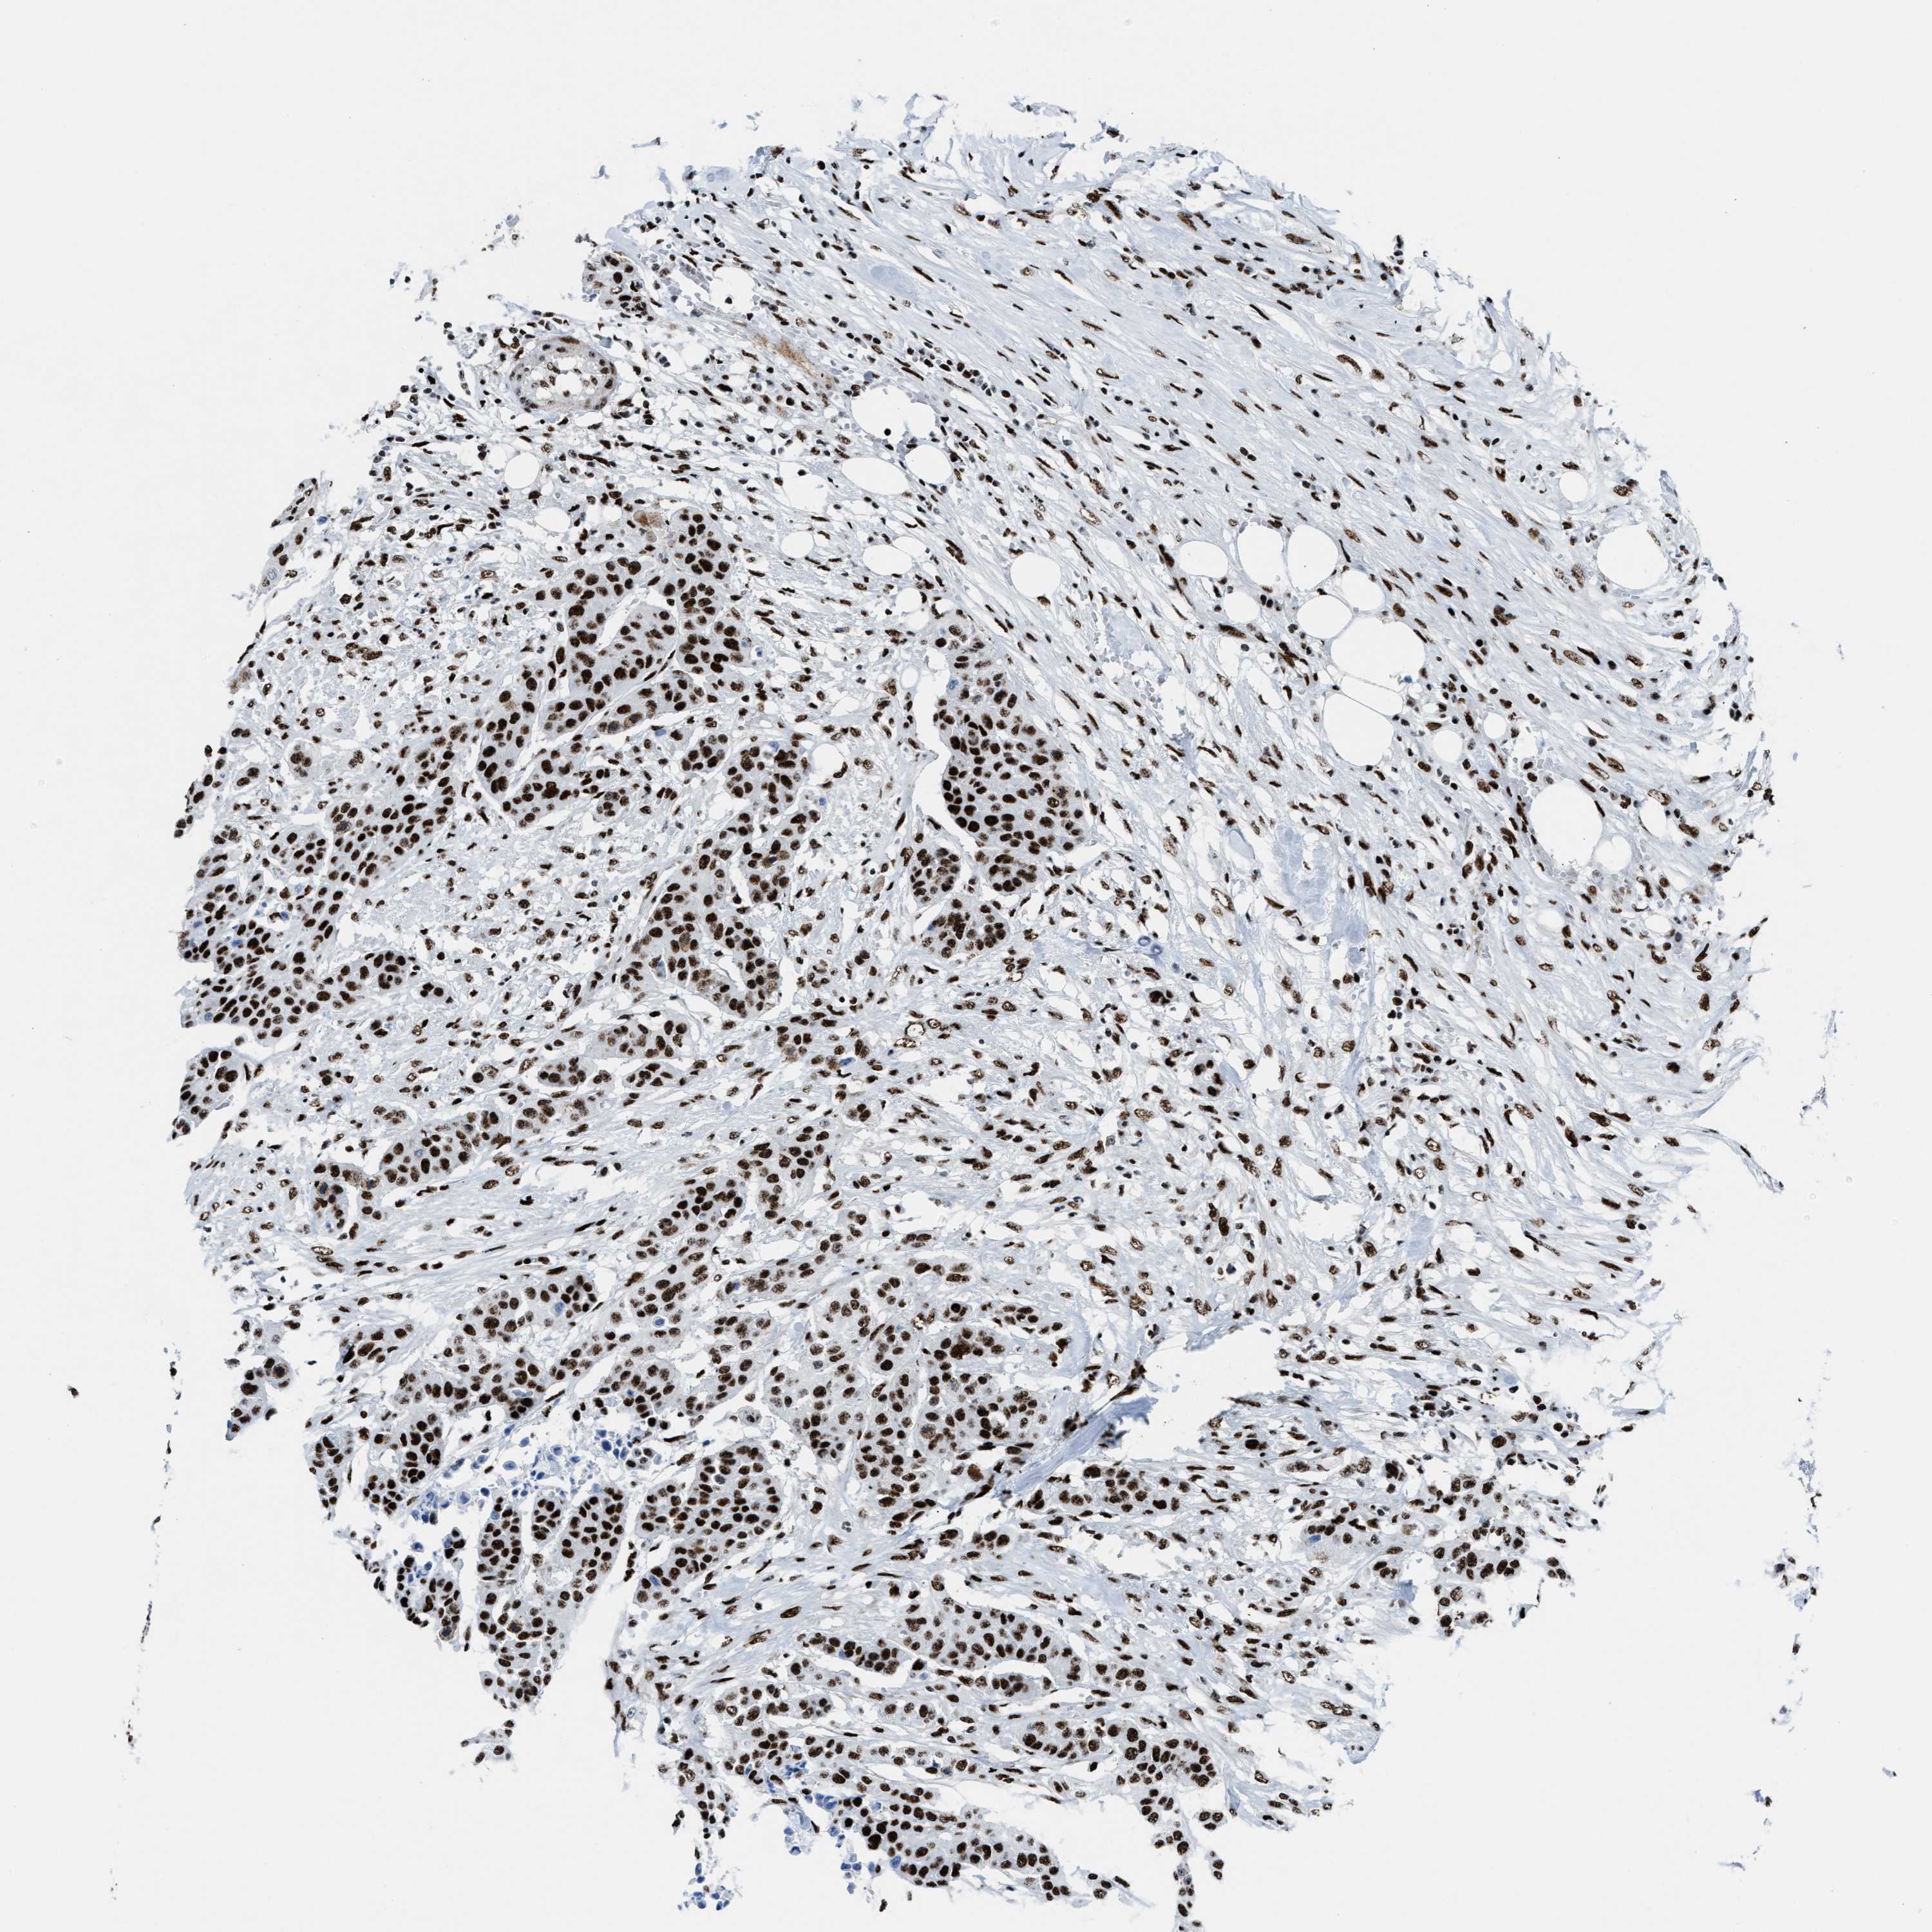

UROTHELIAL CANCER - Protein expressioni

A mouse-over function shows sample information and annotation data. Click on an image to view it in a full screen mode. Samples can be filtered based on level of antibody staining by selecting one or several of the following categories: high, medium, low and not detected. The assay and annotation is described here.

Antibody stainingi

Antibody staining in the annotated cell types in the current human tissue is reported as not detected, low, medium, or high, based on conventional immunohistochemistry profiling in selected tissues. This score is based on the combination of the staining intensity and fraction of stained cells.

Each image is clickable and will lead to virtual microscopy that enables deeper exploration of all samples and also displays staining intensity scores, fraction scores and subcellular localization as well as patient and tissue information for each sample.

Antibody HPA054094

Antibody HPA054559

Antibody CAB022069

Staining

High

Medium

Low

Not detected

Intensity

Strong

Moderate

Weak

Negative

Quantity

>75%

75%-25%

<25%

None

Location

Nuclear

Cytoplasmic/membranous

Cytoplasmic/membranous,nuclear

Urothelial carcinoma, High grade

Urothelial carcinoma, NOS

Urothelial carcinoma, Low grade